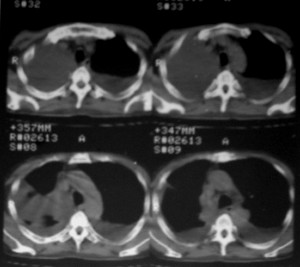

右侧肺癌术后:肝内可见多个大小不等的低密度结节影。腹腔及双侧胸腔大量积液。考虑:肺癌并胸膜及肝脏转移。

纵隔淋巴结增大,双侧胸水。考虑术后残留,而非复发。

肺癌术后 。双侧胸水 纵隔 胸膜 肝脏转移